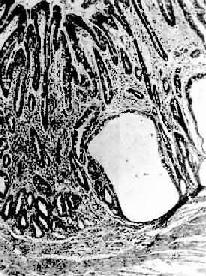

图10-3 慢性萎缩性胃炎

幽门腺大部分萎缩消失,胃小凹延长,有潴留性小囊形成,腺上皮中杂有不少杯状细胞(肠上皮化生),固有膜内有不少慢性炎性细胞浸润(Ⅱ74-4950)